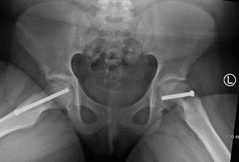

In situ fixation

In this X-ray, two screws have been inserted in the patient's right hip to stop progression of a slip. A single screw has been inserted in the left hip to prevent SCFE from developing.

Reproduced from Woiczik MR, Pizzutillo PD, Gross RH, Carroll KL: Musculoskeletal effects of Down Syndrome. Orthopaedic Knowledge Online Journal 2012; 10(10). Accessed June 2016.